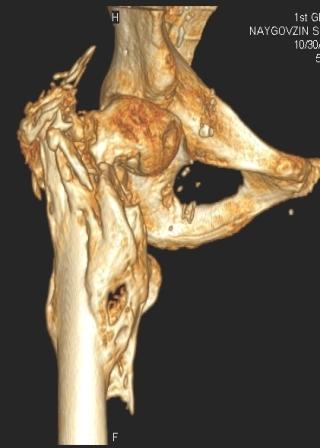

[Ortho] Сросшийся со смещением чрез-подвертельный перелом

Больной Н. 44 года травма 1,5 года назад июнь 2008 года чрез-под вертельный  перелом правого бедра. Во время лечения у больного развился алк делирий,  проводилось консертативное лечение перелома.

На КТ перелом сросся за счет костной мозоли.

Протез? Если <да> Можно ли обойтись стандартной ножкой Corail?

Или межвертельная остеотомия?